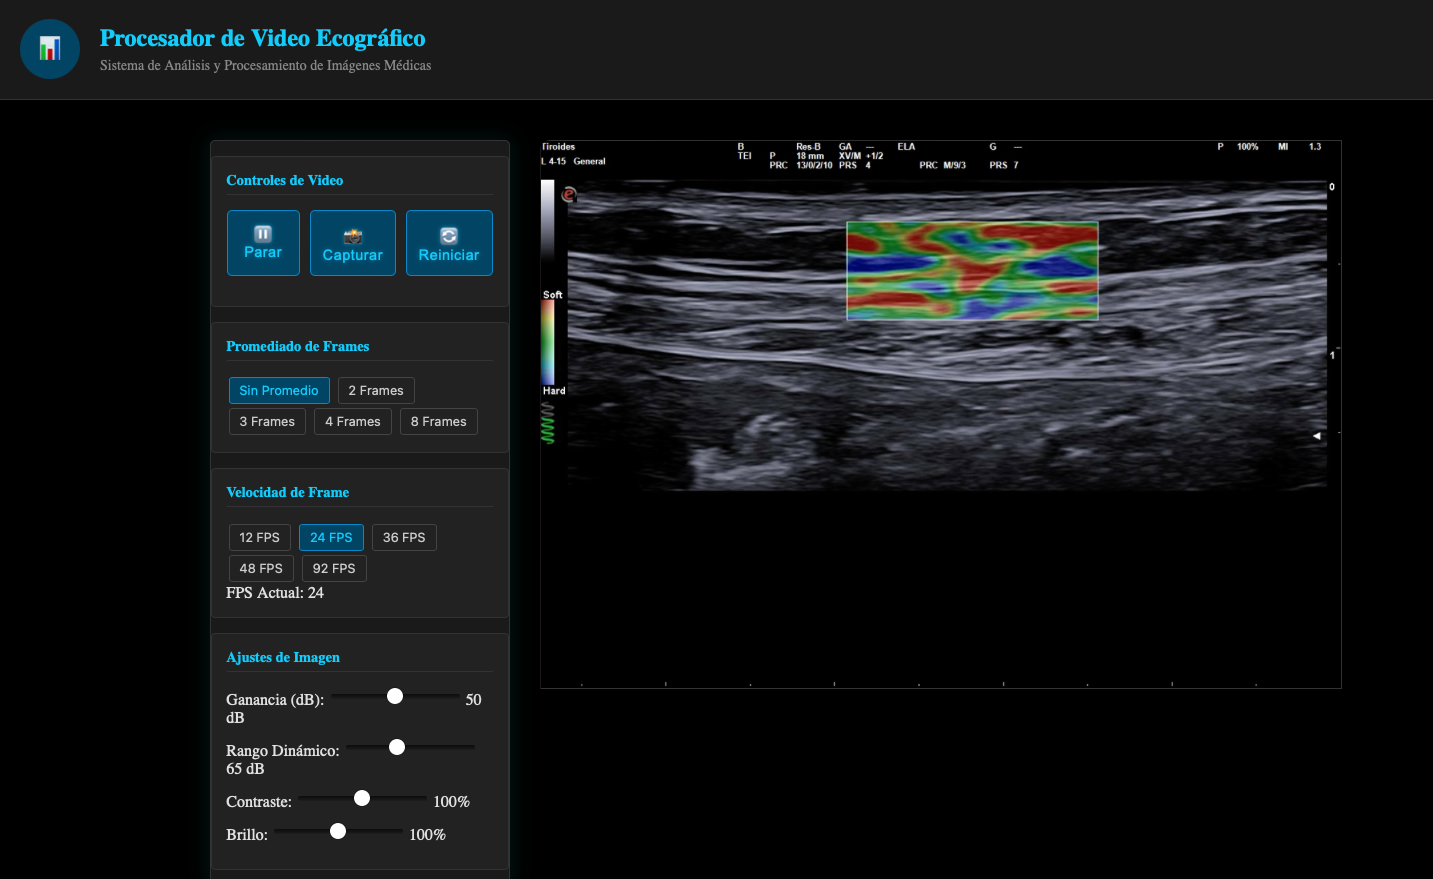

Esta intefaz de usuario, la podras encotnar en el modulo del curso II: Parametros nivel avanzado ( pronto)

Postproceso en Ecografía

El postproceso en ecografía se refiere a los pasos que se realizan después de capturar las imágenes o videos para optimizar la interpretación y el uso clínico de los datos obtenidos. Esta etapa incluye ajustes, almacenamiento, análisis y generación de informes, permitiendo una mejor documentación y comprensión de los hallazgos ecográficos.

Video

La grabación de video en ecografía permite documentar secuencias en tiempo real, como el movimiento del corazón o el flujo sanguíneo en un vaso. Esto es especialmente útil en estudios dinámicos, como los realizados con Doppler color, donde las imágenes fijas no capturan adecuadamente la funcionalidad o el patrón de flujo observado.

Persistencia

La persistencia controla el grado de suavizado aplicado a la imagen al promediar múltiples fotogramas. Una alta persistencia genera imágenes más suaves, reduciendo el ruido, pero puede sacrificar la capacidad de detectar movimientos rápidos, como el flujo sanguíneo. En estudios dinámicos como el Doppler, se prefiere una persistencia baja para capturar los cambios en tiempo real.